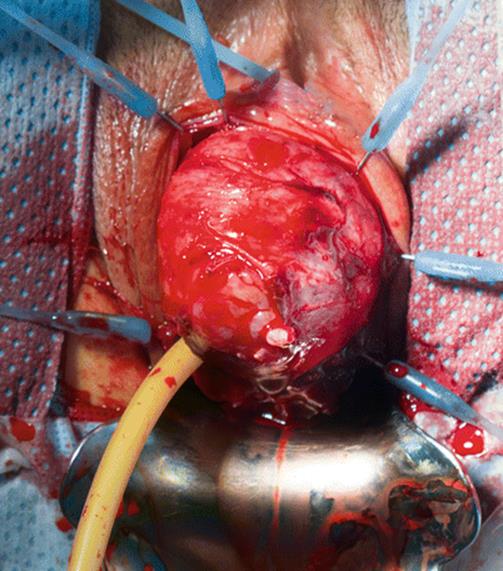

8.13 Large Urethral Leiomyoma Causing Urethral Obstruction

During her second pregnancy, the young patient in Figs. 8.43, 8.44, 8.45, 8.46, 8.47, 8.48, 8.49, 8.50, 8.51, 8.52, 8.53, 8.54, 8.55, 8.56, 8.57, and 8.58 presented with difficulty in voiding, tenderness in the anterior vaginal wall, and the feeling of a mass. Physical examination revealed a large, nontender, elastic, nonmobile mass inferior to the pubic bone. The mass displaced the urethra inferiorly.

Fig. 8.48

The mass is mobilized and freed from the surrounding structures. The arrows outline the tumor before removal

Fig. 8.49

The mass has been removed, and the remaining adhesions have been transected